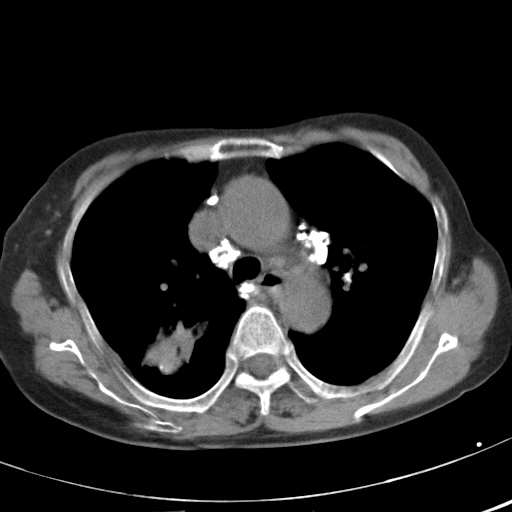

以下是引用hhcckk在2007-3-2 14:51:00的发言:[br]考虑结核球可能性大,依据[br]1病灶在下叶背段,结核的好发部位[br]2病灶内有大量的钙化,纵隔内有大量的淋巴结钙化[br]3重要的是半年前与现在相比无变化,假如是肿瘤的话不会这么‘善良’[br]4病灶周围卫星灶不明显,病灶有毛刺,胸膜凹陷,肿瘤不能完全排除,有条件的话最好做个活检

以下是引用liuyue在2007-3-2 17:15:00的发言:[br]1位置:右上叶后段[br]2性质:大分叶、粗长毛刺、条状斑片状钙化、纵隔多发淋巴结钙化,无强化,故考虑:肺结核灶(陈旧)